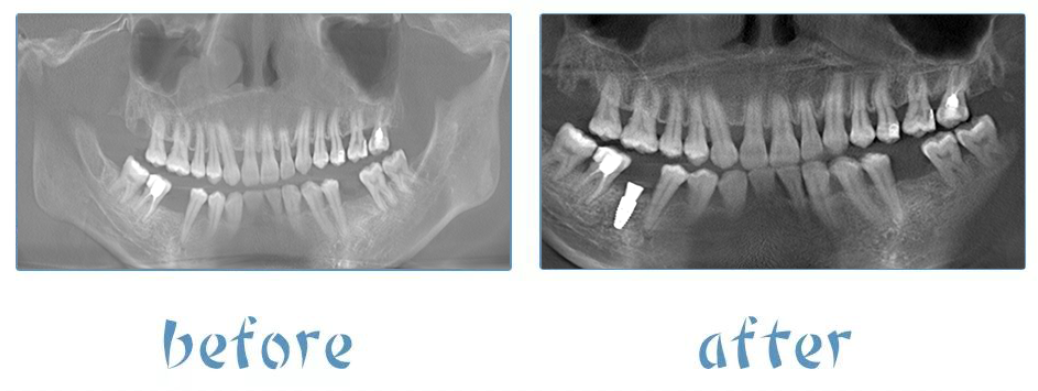

今天接受姚江武院长亲自种植的患者——陈女士,35岁,两侧各有一颗牙齿缺失多年,近几年开始重视口腔健康,关注牙齿种植。

由于缺牙时间长,牙槽骨出现萎缩,骨头厚度薄,种植难度较大,姚江武院长使用全程导板,精准微创种植,5分钟快速完成种植牙手术 ,让张女士实现了缺牙重生的夙愿。

此次接受姚江武院长种植手术的陈女士,是厦门麦芽口腔医院首例瑞士士卓曼数字化导板种植。

种植体选用的是瑞士士卓曼研发的“瑞锆”种植体,表面处理好,加速成骨,一般种植体需要三个月后进行牙冠修复,瑞锆种植体则在一个月到一个半月后即可进行取模修复。

姚江武院长则使用数字化全程导板,精确控制种植体的植入方向与深度,使手术过程更安全。